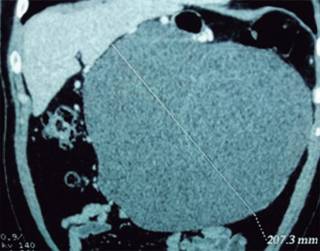

Paciente de 45 años con dolor abdominal generalizado, estreñimiento y náusea posterior a la alimentación. La radiografía de abdomen evidencia en el epigastrio imagen redondeada homogénea de mayor densidad, que desplaza las asas intestinales y el estómago. La tomografía muestra una imagen ovoidea de 20.8 centímetros de eje mayor (Figuras 1 y 2), con bordes lisos, septos delgados internos y densidades líquidas, proveniente de la raíz del mesenterio, sin conexión con otra estructura, con desplazamiento de las asas y el riñón derecho (Figuras 3 y 4).

Figura 1: Imagen simple de tomografía computada. Corte axial a nivel de ambos riñones donde se observa una imagen redondeada de 20.8 cm en su eje mayor, bien delimitada, de pared fina, con densidades líquidas internas y septos finos.

El diagnóstico por imagen y confirmación patológica fue de quiste mesentérico gigante.